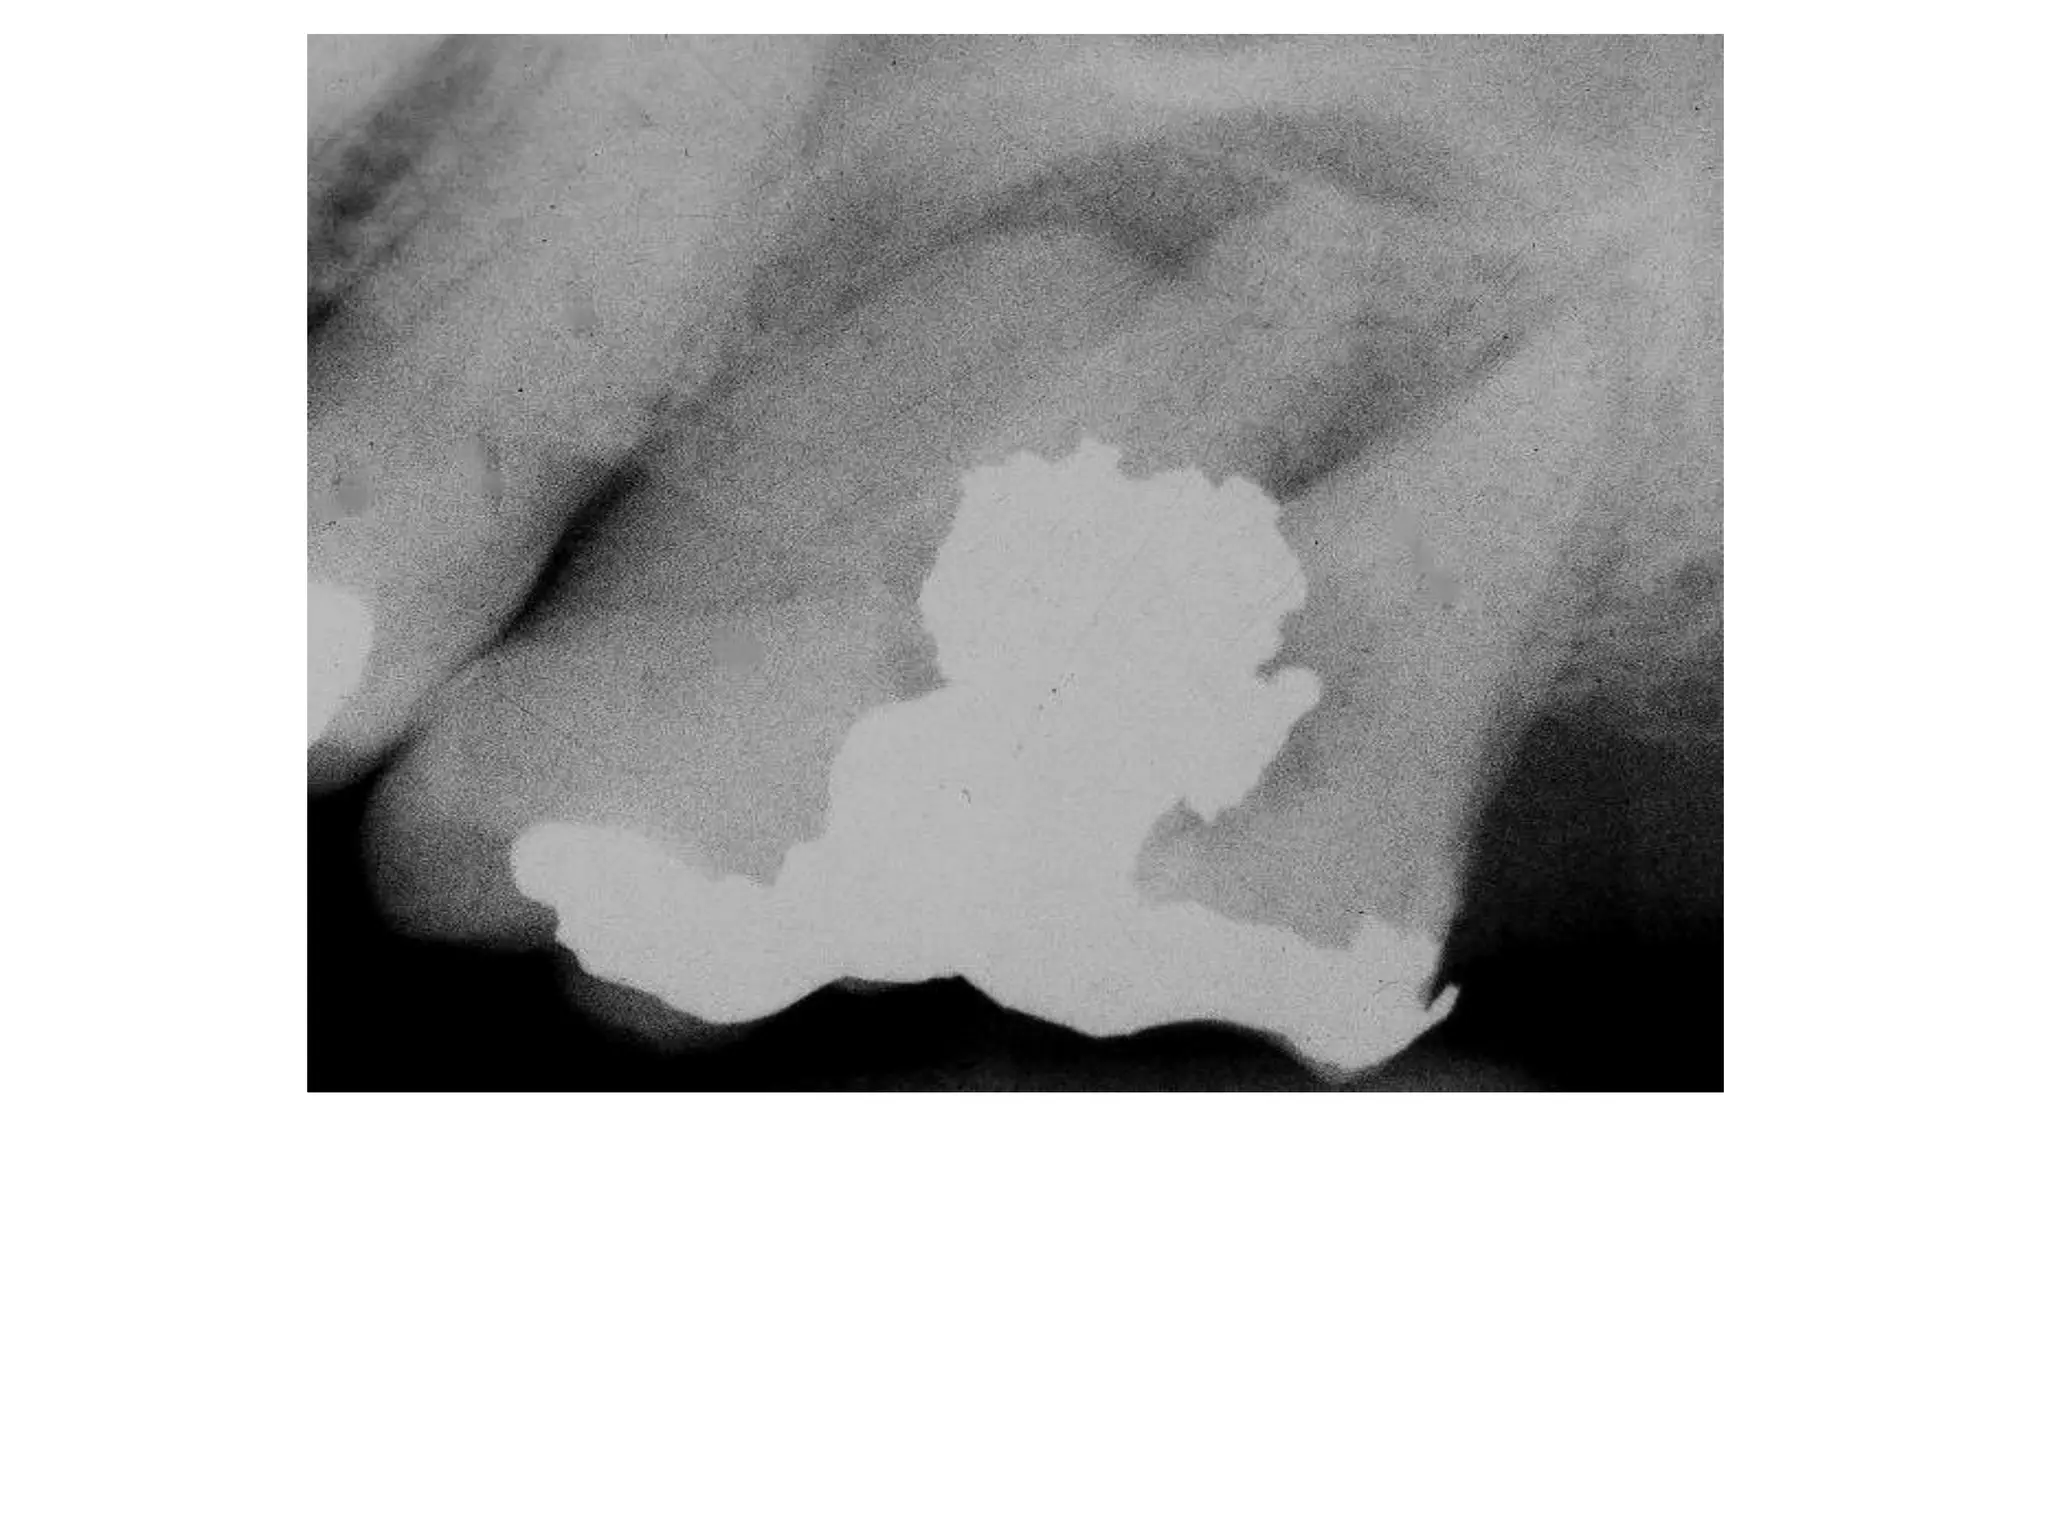

Restorative Materials

Radiopaque: Structures with higher object

density, such as amalgam, gold, silver

points, pins, gutta percha, porcelain.

porcelain

crowns

Ceramic Crowns

crown

amalgam

cast post

gutta percha

silver points